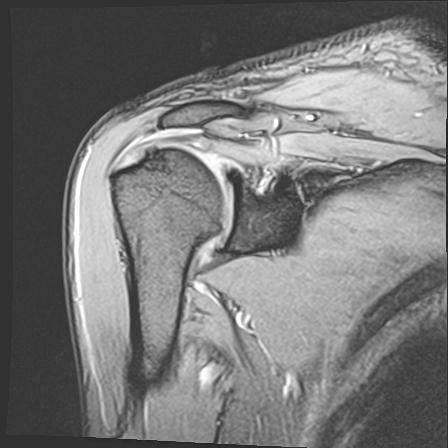

60058 3/9 11/4 右肩 2R+MRI 73歳男性 肩腱板損傷